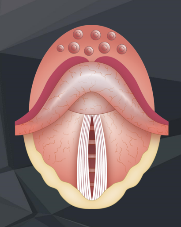

- Glottis

Die Glottis kann entweder ganz geöffnet, fast geschlossen oder ganz geschlossen sein.

ÜBUNG 2.1:

Strecke Deine Zunge heraus und atme mit weit offenem Mund durch diesen ein und aus. Fühle, dass die Stimmritze nun offen ist.

ÜBUNG 2.2:

Sage mit geöffnetem Mund „Aaaaaaahhhhhh“ und atme dabei durch den Mund ein und aus. Bei dieser Übung ist die Stimmritze durch die schwingenden Stimmbänder fast geschlossen.

ÜBUNG 2.3:

Strecke die Zunge heraus, atme durch den Mund ein und halte danach die Luft an. Fühle, dass dabei Deine Stimmritze beim Luftanhalten schließt und vollständig geschlossen ist.

Einatmung

Luft anhalten

Weicher Gaumen

Man kann sich die Stellung des weichen Gaumens durch folgende Übungen bewusst machen:

Geöffnete Stellung

Geschlossene Stellung

ÜBUNG 2.4.:

Atme mit geöffnetem Mund durch diesen ein und aus. Die Stellung des weichen Gaumens bleibt dabei offen. Anatomisch gesehen könnte die Luft auch durch die Nase entweichen. Da der Luftraum zum Mund jedoch viel weiter und größer ist, nimmt die Ausatemluft den Weg des geringsten Widerstandes durch den Mund.

ÜBUNG 2.5:

Atme einmal durch den geöffneten Mund ein und aus und danach bei geöffnetem Mund durch die Nase ein und aus. Fühle wie sich die Stellung Deines weichen Gaumens dabei verändert. Bei Nasenatmung ist der weiche Gaumen verschlossen, da der Luftstrom sonst den Weg durch den Mund nimmt.

Wir können uns die offene und geschlossene Stellung auch durch Sagen von „Bbbbbbb“ (weicher Gaumen offen) oder „Mmmmmm“ (weicher Gaumen geschlossen) bewusst machen.

- Zunge

Die Zunge kann den Mundraum in den vorderen und hinteren Mundraum unterteilen. Das ist an drei unterschiedlichen Stellen möglich und zwar durch das Sprechen der Buchstaben T (Verschluss vorne knapp hinter den oberen Zähnen), CA (Verschluss mittig) oder des arabisch gehauchten H (Verschluss hinten – geht auch mit CH)

Der sogenannte T-Verschluss kann auch mit den Buchstaben D oder N durchgeführt werden.

Beim Tauchen kann der Mund – bedingt durch das Mundstück des Atemreglers – nicht dicht verschlossen werden. Insofern wird beim Druckausgleich mittels Valsalva-Manöver immer eine der drei möglichen Verschlussarten (T, CA oder H) durch die Zunge benutzt um die Luft aus der Lunge vom hinteren Mundraum weiter in den Nasenraum zu drücken.

ÜBUNG 2.6:

Versuche einmal das oben abgebildete T-Verschluss-Valsalva-Manöver. Wenn Du es richtig durchführst, blähen sich bei zugehaltener Nase ganz leicht Deine Nasenflügel auf – ein Zeichen, dass Du es richtig gemacht hast. Spüre dabei, dass Deine Stimmritze offen bleibt!

ÜBUNG 2.7:

Beim Druckausgleich nach Frenzel mit Zunge in T-Stellung bleibt die Stimmritze geschlossen, da die Luft zum Druckausgleich nicht aus der Lunge kommt, sondern aus dem Mundraum nach oben in den Nasenraum gedrückt wird.

Bei beiden Techniken ist der weiche Gaumen natürlich offen!

Versuche beide Druckausgleichtechniken nun mit allen unterschiedlichen Zungenverschlüssen: T, Ca und H.

Sowohl beim Valsalva- als auch beim Frenzel-Manöver muss der weiche Gaumen natürlich offen sein und den Weg zum Nasenraum freigeben. Beim Valsalva ist die Stimmritze offen, beim Frenzel geschlossen (s. Bilder oben).